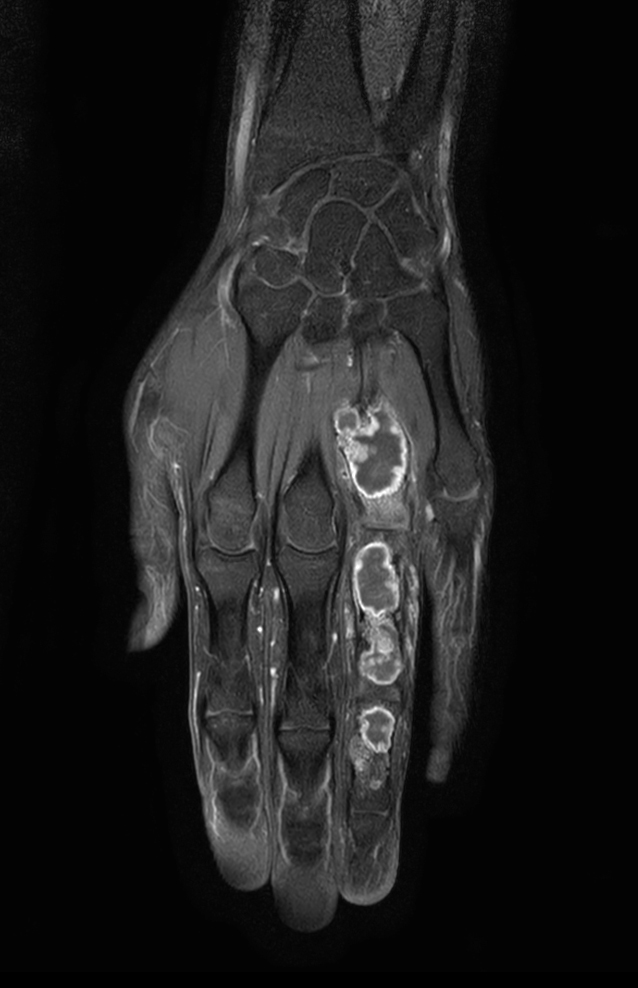

Coronal T1w mDIXON XD TSE (Water only)

Coronal T1w mDIXON XD TSE (In Phase)

Coronal T1w mDIXON XD TSE (Partial FatSat)